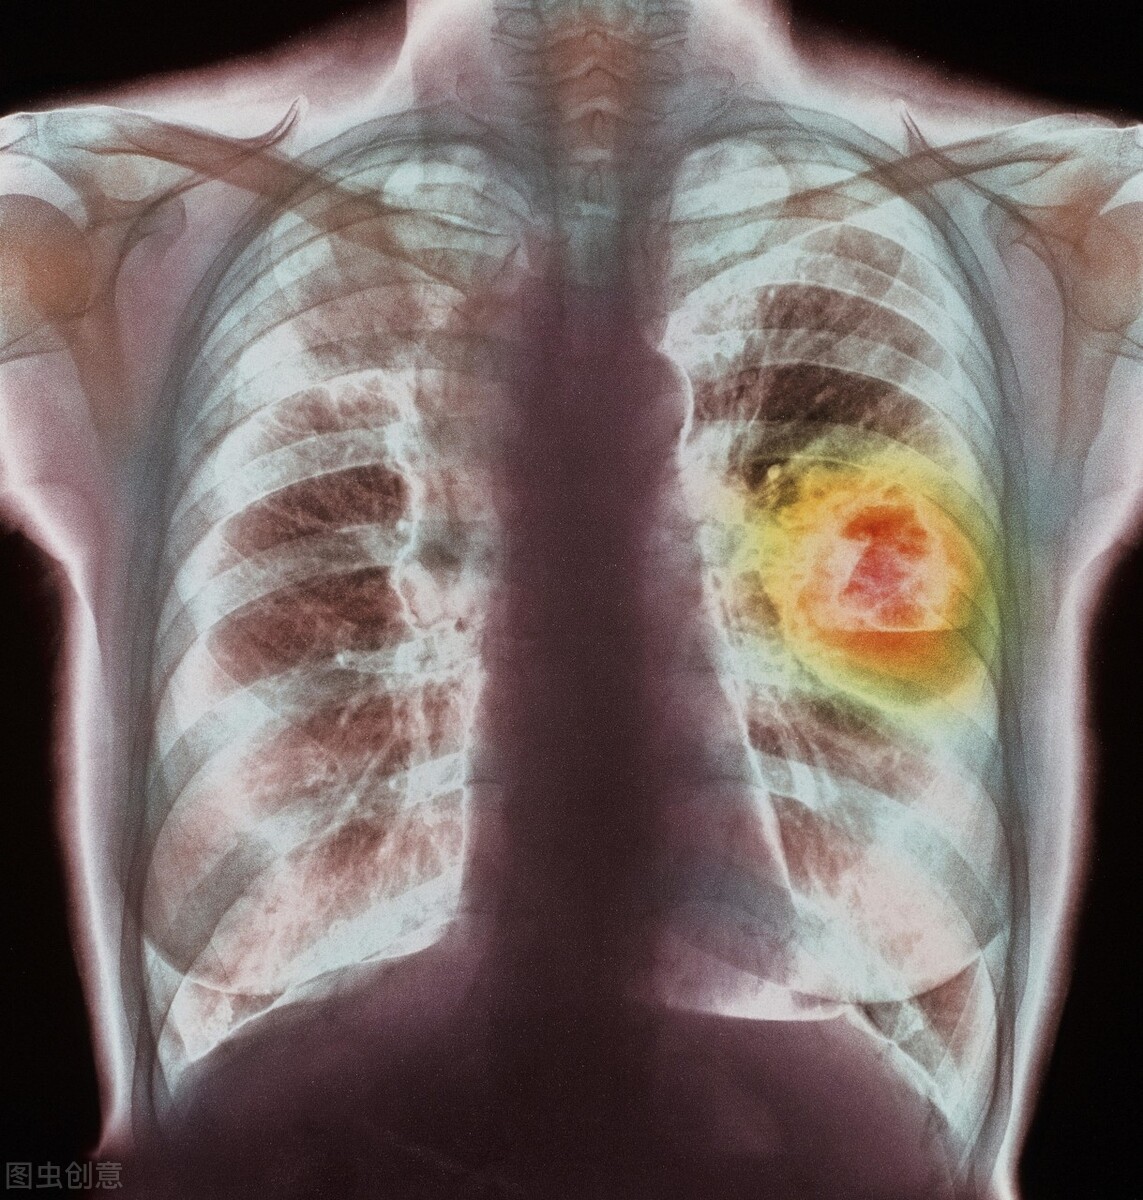

于是张女士前几天去医院做了检查,但是医生的给出的诊断结果却是他们不能接受的,医生最终诊断为肺癌晚期,张女士和家人都纳闷,怎么就会患肺癌,自己也不抽烟,就连老伴10年前也戒烟了。这是怎么回事呢?原来啊,张女士平常生活比较节俭,做饭的时候嫌开油烟机比较费电,都是打开窗户,从不开油烟机,因为炒菜时弄得家里油烟味很大,家人多次劝她开油烟机,但她还是依然不听,长此以往吸入油烟,最终诱发肺癌。

其实这样的事情还有很多,湖北的李婆婆3年前诊断出肺癌,因为家住农村,家里没有装油烟机,但是好在他们家厨房比较通畅,排烟比较好,但是李婆婆有习惯,就是等油烧热以后再放菜,她说这样炒出来的菜才香。我们都知道油的沸点是300℃,但是将油加热到170℃的时候,油就开始汽化分解,形成小油滴和油烟,等到加热到270℃时,高沸点食用油就开始汽化,可以看见明显的青色油烟。油烟中的主要成分是丙烯醛、苯并芘、二苯并蒽等,它可以刺激我们的鼻、眼、咽喉黏膜等,损伤呼吸道黏膜,长此以往很容易诱发肺癌。这种病因在中老年女性肺癌患者*特中**别突出,危险性达正常人的2~3倍。